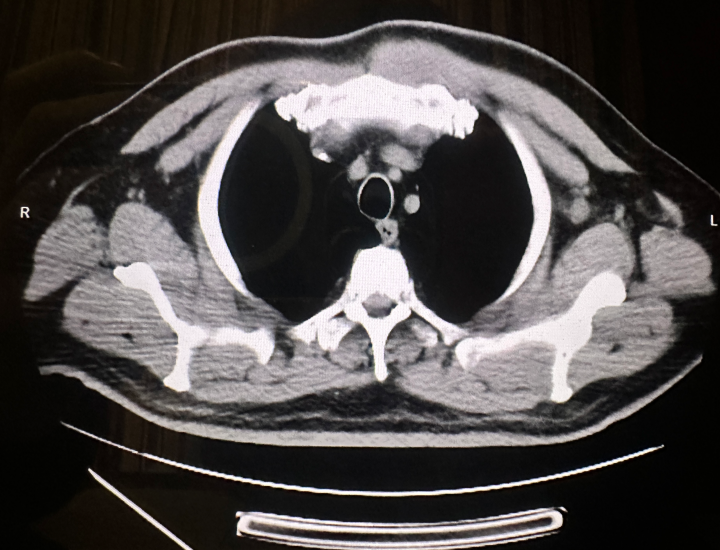

在后续治疗过程中,患者出现胸骨柄处包块(23 mm×12 mm)(图2)。2025年7月31日复查:血常规白细胞7.95×109/L,血红蛋白122 g/L,血小板169×109/L;免疫球蛋白IgA 13.5 g/L,κ轻链5.68 g/L,M蛋白10.6%;乳酸脱氢酶353 U/L;骨髓常规示原幼浆细胞占58.0%,MRD 16.95%。PET/CT示胸骨骨质破坏,周围软组织肿胀,较大横截面积4.3 cm×4.0 cm,SUVmax 20.9;全身多发骨骼弥漫性FDG代谢增高,SUVmax 7.7~12.2(图3)。

图3. PET/CT检查结果